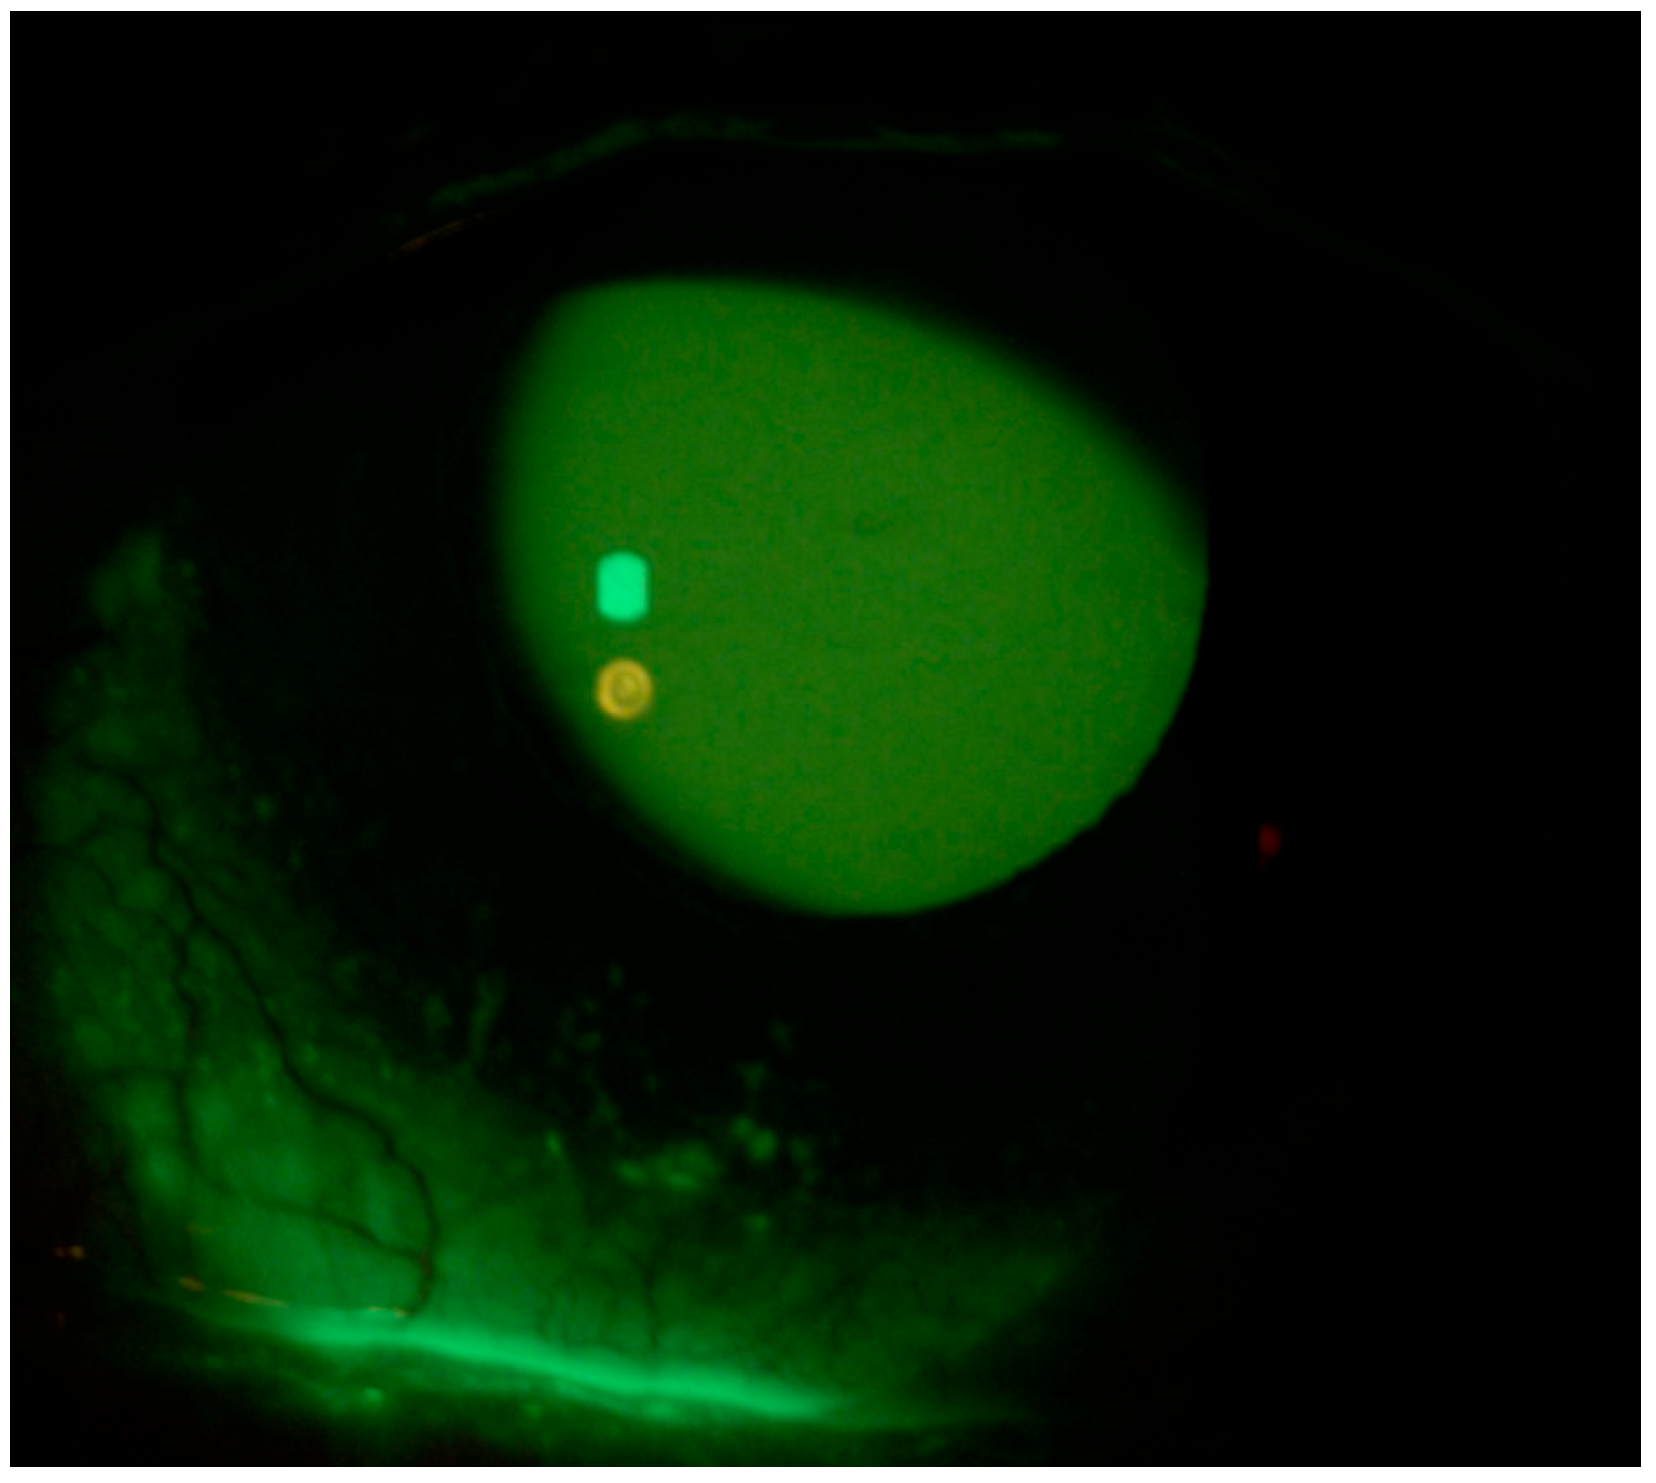

A 59-year-old Caucasian male patient with a past medical history of mild dyslipidemia received three doses of the Cominarty (Pfizer-BioNTech) vaccine for SARS-CoV-2 (with the last dose administered 7 months before coming into our observation). The patient was evaluated for the presence of about six weeks’ ocular burning in both eyes, which was associated with foreign body sensation, and symptoms of asthenopia—characterized by visual fatigue, ocular discomfort, blurred vision, and frontal headaches triggered or worsened by prolonged near tasks, particularly during video terminal work (VDT). These symptoms began a few days after the patient contracted COVID-19. He had a fever in his first three days of the COVID-19 illness, which was associated with persistent upper respiratory congestion; molecular buffer negativization was detected 9 days after the first positive RT-PCR test. He also reported that he had never noticed any previous ocular surface disturbances or foreign body sensations. Ophthalmological examination showed a best-corrected visual acuity of 0.0 LogMar in both eyes; reduced lacrimal meniscus in both eyes; punctate epitheliopathy in the lower corneal sectors of right (CLEK: 2) (Figure 1) and left eye (CLEK: 3) (Figure 2), according to the Collaborative Longitudinal Evaluation of Keratoconus (CLEK) grading system; slight cortical clouding of the lens in both eyes; normal ocular ductions; mild exophoria and convergence deficit, with a proximal point of convergence (PPC) of 38 cm; and no pathological findings in the fundus oculi in both eyes.

Figure 1.

Right eye at presentation (Fluotest).